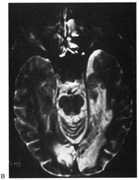

Fig. 5. Macula-splitting hemianopia. A 47-year-old man with AIDS and sudden onset of poor vision. A. Fields show complete left hemianopia. B. MRI shows lesion of right lateral occipital cortex, affecting distal optic radiations. Biopsy showed nonspecific encephalitis.

The optic radiation may be affected anywhere in its course (see Chapter 4); the type of visual field defect reflects the site of damage. Ischemic or hemorrhagic lesions of the internal capsule affect the optic radiation while it is still a relatively compact bundle, usually causing a complete homonymous hemianopia. A similar defect can arise from damage close to the termination in striate cortex (Fig. 5). Lesions of the ventral fibers in the anterior temporal lobe cause a contralateral superior visual quadrant defect (Fig. 6). Most often this defect aligns on the vertical meridian, with variable extension toward the horizontal meridian and central vision.33 Lesions of the dorsal fibers in the parietal lobe cause an inferior visual quadrant defect (Fig. 7). Because there is no sharp demarcation of the dorsal fibers from the ventral fibers in this portion of the posterior pathway, the defect seldom aligns along the horizontal meridian.33 Overall, quadrantanopia is more frequent with lesions of striate cortex.33 Lesions of the temporal lobe more than 8 cm posterior to its anterior tip can affect both upper and lower radiations. Small lesions also may affect certain portions of the radiations and spare others; for example, damage to the midportion of the optic radiation can mimic the sectoranopias of LGN lesions (Fig. 8).34 Although there can be some incongruity to the visual field defects of optic radiation lesions, this is less marked than the incongruity with optic tract lesions.